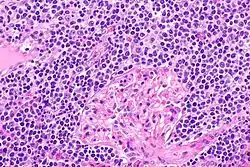

EMZL infiltrating kidney tissue.

The histopathologic (i.e. microscopic) examination of EMZL lesions typically reveals a vaguely nodular or diffuse pattern of cells. The malignant cells in these lesions have, in varying proportions, the morphology of small-to-medium-sized lymphocytes, centrocyte-like B cells, centroblast-like B cells, monocyte-like B cells, plasma cell-like B cells, and/or large B cells. When the large B cells form prominent sheets that are clearly separated from cells with the other, low-grade malignant morphologies, the disease may be transforming to the far more aggressive malignancy, diffuse large B-cell lymphoma. This transformation occurs in ~18% of patients at a median of 4–5 years after the original diagnosis of EMZL.[22] Immunophenotyping or the neoplastic large B cells in these lesions shows that they express CD20 but not CD3 surface membrane B cell marker proteins. The cells almost always express BCL2 and may express MNDA (~70% of cases), CD23 (~33% of cases) and CD5 (~20% of cases) marker proteins but do not express the cyclin D1 marker protein.,[22] the T-cell marker, CD10, or BCL6.[1]